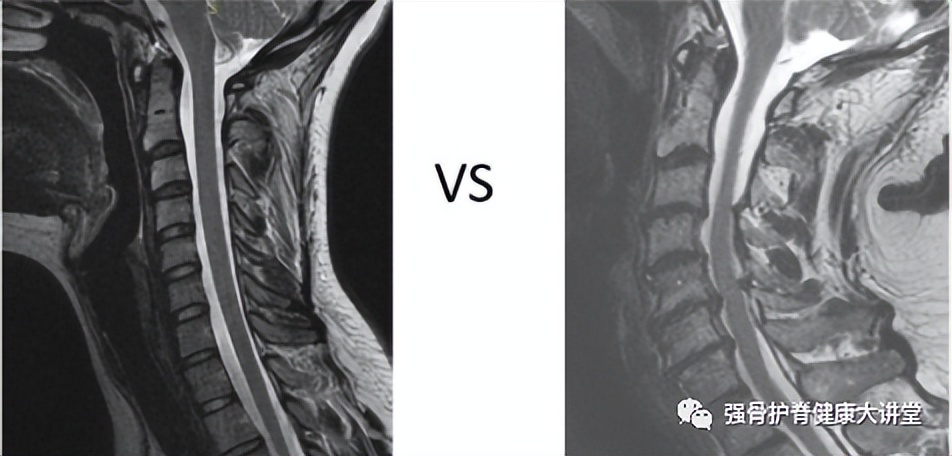

正常vs异常颈椎MRI(图片来源于网络)